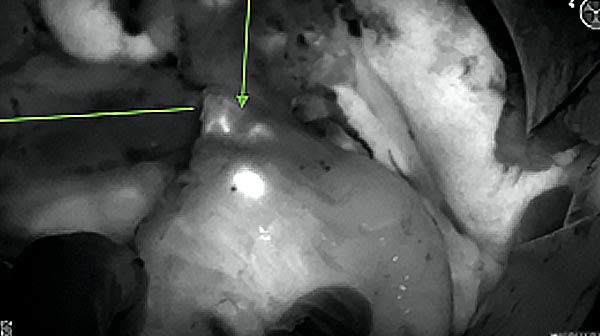

Intraoperative fluorescence imaging of the pancreas part that contains tumor

The tumor area light up fluorescently and so does a lymph node (LN; red circle) that is located on top of the tumor area. We can also see some lymphatic ducts (green circle).

After removal of the pancreas tumor fluorescence imaging was performed to check that there was no residual fluorescence left in the wound bed. A little bit of background fluorescence was found in the intestine.